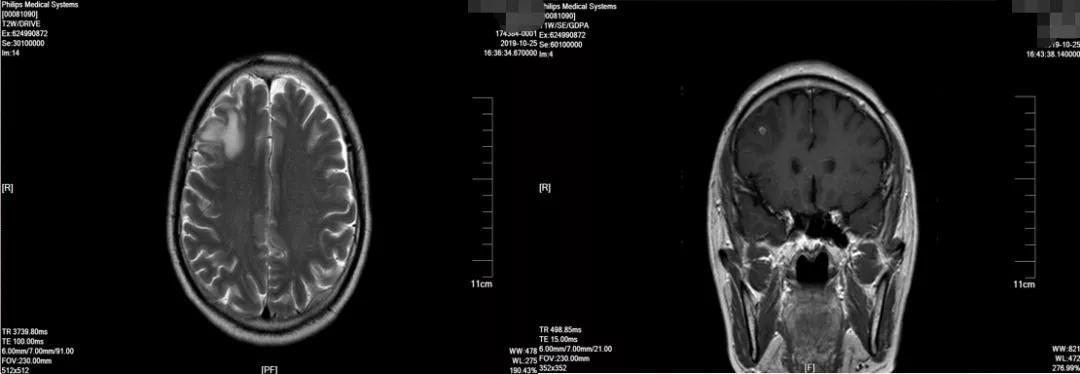

2019-10-25于广医一院行PET/CT检查考虑右上肺肺癌并右肺门、纵隔淋巴结转移。头颅MR:右侧额叶异常信号影, 考虑转移瘤。 双侧额顶叶散在缺血灶。

2019-10 头颅MRI示右额叶转移瘤,伴瘤旁水肿